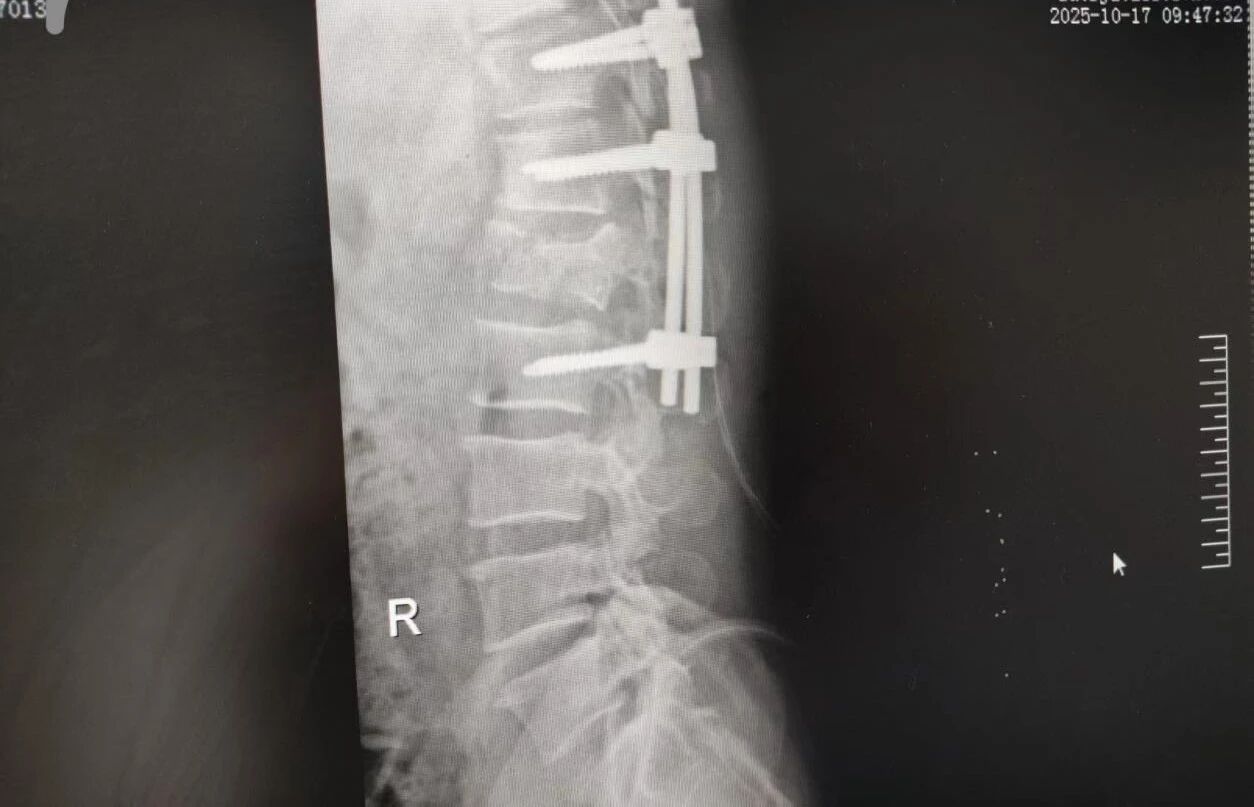

針對(duì)腰椎傷情,骨科竇志剛醫(yī)生團(tuán)隊(duì)緊急開(kāi)展腰 1 椎體爆裂性骨折切開(kāi)復(fù)位內(nèi)固定術(shù) + 椎板切除減壓術(shù)。手術(shù)室、麻醉科無(wú)縫銜接開(kāi)通綠色通道,手術(shù)團(tuán)隊(duì)快速就位,術(shù)后患者下肢活動(dòng)恢復(fù)自如。